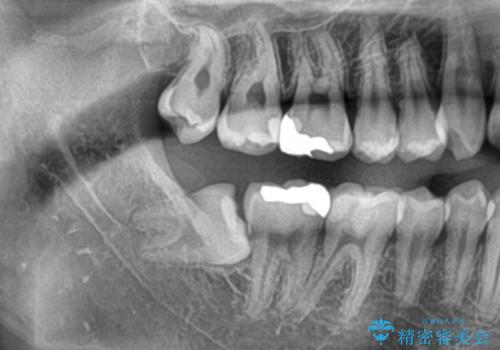

- 親知らずが痛くて抜きたいと来院。

CTを撮影し、神経の位置など確認し安全なことを確認して抜歯を行いました。